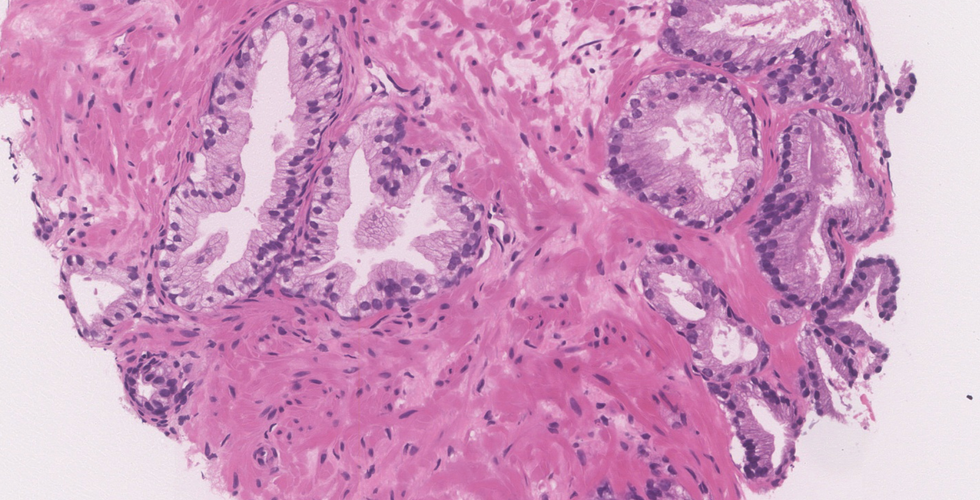

This case shows crowded discrete small glandular proliferation, with few poorly formed/fused glands and occasional cribriform pattern, infiltrating in between benign glands

Glands have sharp lumina occasionally containing crystalloids; the cytoplasm is amphophilic, distinct from adjacent benign glands which has a pale character.

Nuclei are enlarged and hyperchromatic with prominently enlarged nucleoli

Acinar adenocarcinoma: Microscopic features

● Diagnosis requires a number of features such as architectural, nuclear, cytoplasmic, and luminal changes.

● Proliferation and crowding of uniform, small acini having irregular contours, which infiltrate between adjacent benign prostate glands.

● Acini are lined by a single layer of epithelial cells; basal cell layer is absent (basal cell IHC markers such as p63 and HMWK are negative)

● Nuclei are large, hyperchromatic with one or more prominent macronucleoli

● The cells are cuboidal or columnar with amphophilic cytoplasm (compared to more pale/foamy cytoplasm of adjacent benign prostatic glands)

● Various patterns are seen in high grade tumors including poorly formed/fused glands, cribriform/glomeruloid glands, cords, sheets or single cells